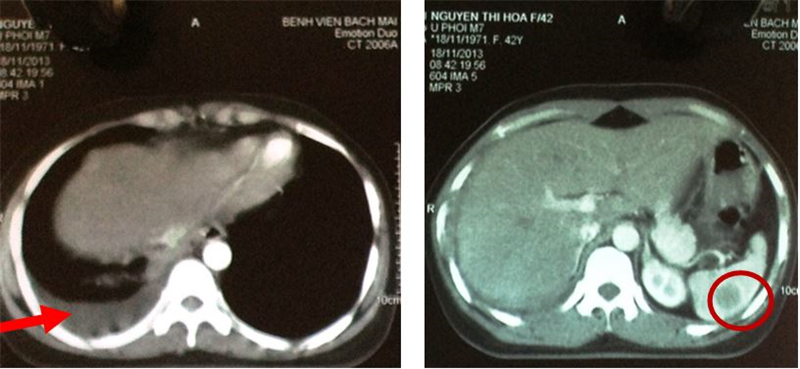

1. Xạ hình xương:

• Tăng hoạt độ phóng xạ tại đốt sống ngực 10, khớp cùng chậu hai bên (hình 5)

Hình 5: Trên xạ hình xương thấy hình ảnh tăng hoạt độ phóng xạ (đầu mũi tên) tại đốt sống ngực 10 và khớp cùng chậu hai bên.

1. Xạ hình xương (sau 5 tháng điều trị): Tăng hoạt độ phóng xạ tại đốt sống ngực số 10, cung trước xương sườn 9,10; xương chậu bên trái (đầu mũi tên hình 11)

Hình 11: Xuất hiện thêm tổn thương xương sườn trên xạ hình xương (bệnh nhân bị va đập vào vùng mạn sườn phải do tai nạn trước khi làm xét nghiệm xạ hình xương)

So sánh trước và sau điều trị:

Xạ hình xương trước điều trị: tăng hoạt độ phóng xạ (đầu mũi tên) tại đốt sống ngực 10 và khớp cùng chậu hai bên

Xạ hình xương sau điều trị: Tăng hoạt độ phóng xạ tại đốt sống ngực số 10, cung trước xương sườn 9,10; xương chậu bên trái (đầu mũi tên hình 11).

Hình ảnh tăng hoạt độ phóng xạ tại cung trước xương sườn 9,10 tương ứng với vị trí va đập trước khi làm xạ hình xương (vòng tròn vàng).